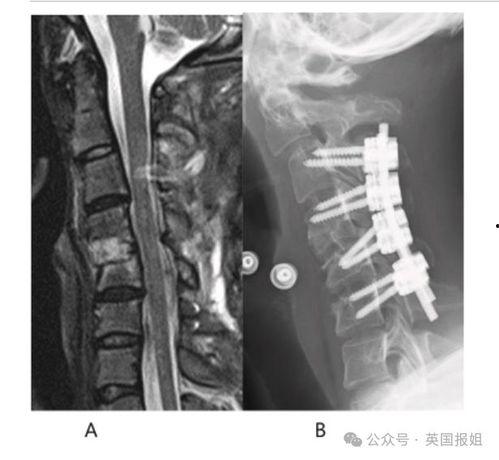

颈椎 日本,日本视角下的预防与康复之道